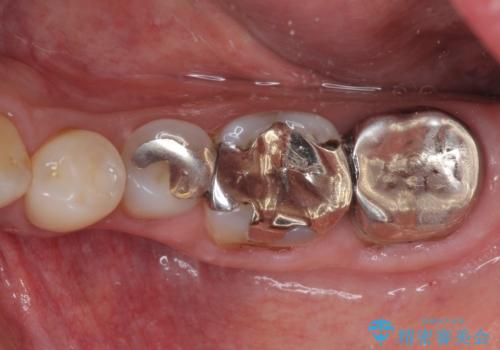

上の奥歯は一部神経を取り除くこととなりましたが、残った神経は正常な状態を保つことができました。

下の奥歯も、虫歯を取り除いて仮歯を装着したことで歯肉の腫れが引き、出血することもなくなりました。